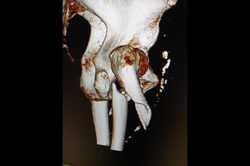

Metarsals with dislocations Lisfranc